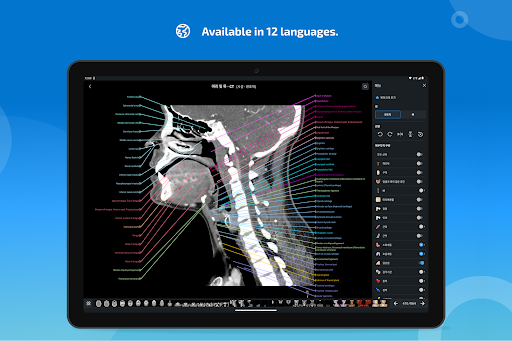

e-Anatomy tiene más de 26 000 imágenes que contienen series de imágenes en vistas axiales, coronales y sagitales, así como radiografías, angiografías, imágenes de disección, gráficos anatómicos e ilustraciones. Todas las imágenes médicas fueron etiquetadas cuidadosamente, más de 967 000 etiquetas disponibles en 12 idiomas, incluida la Terminologia Anatomica latina.

- Cambie de idioma con solo tocar un botón

-El idioma coreano ya está disponible para la aplicación y las estructuras anatómicas.